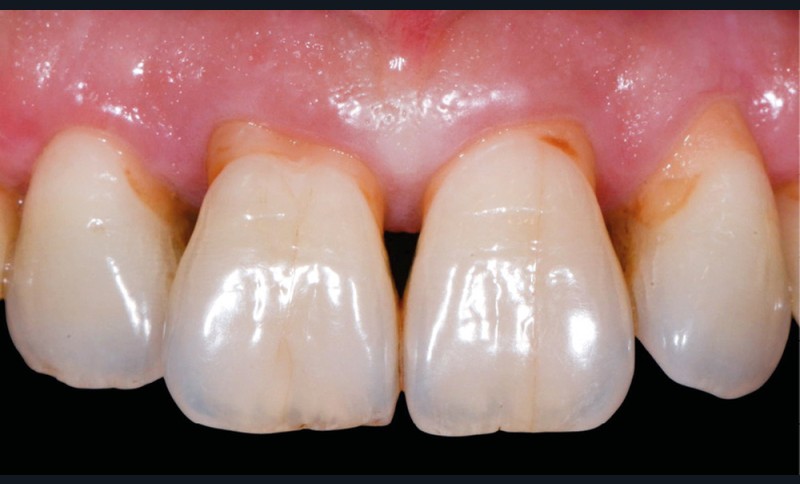

Avant tout traitement, il convient de déterminer l’étiologie des colorations dentaires. Selon leur origine, la stratégie thérapeutique et les informations délivrées au patient peuvent différer. Outre les modifications de couleur inhérentes au vieillissement des dents (fig. 1a), on distingue généralement deux types de dyschromies selon que leur étiologie est intrinsèque ou extrinsèque [2].